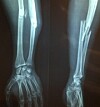

El hueso, es el segundo tejido del cuerpo humano en el que se utilizan más implantes para tratar o reparar lesiones y realizar injertos. Para estos efectos, se emplean materiales de reemplazo óseo sintéticos y biológicos cuya estabilidad mecánica, actividad biológica y aceptación en receptor, siguen siendo una preocupación

La hidroxiapatita (HAP) es parte del de los minerales encontrados en los huesos, pero también, es una biocerámica conocida por ser un material biocompatible que se utiliza en diversas aplicaciones médicas como material para reparar huesos dañados debido a la estrecha similitud con la composición natural del hueso y sus propiedades osteoconductivas.